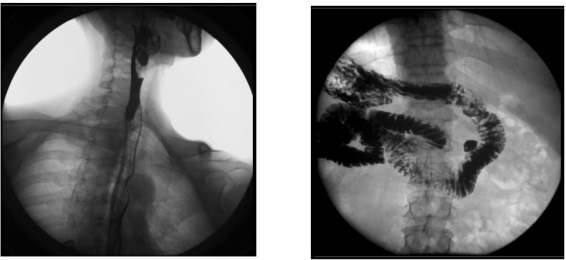

2、数字化胃肠功能:适用于胃肠道造影检查,如食管造影、上消化道造影、全消化道造影等。

2) 肛肠科:可应用气钡双重造影和排便造影(DFG)功能,可检查大肠的细小病变,如小息肉、早期肿瘤、溃疡等效果良好;可检查肛管炎、耻骨直肠肌综合症、骶骨部畸胎瘤、直肠前突、直肠内套叠、肛门直肠损伤和异物等检查。

3、其他造影:适用于各种普通及特殊造影,如口服胆囊造影、静脉胆道造影、T 管造影、逆行胰胆管造影(ERCP)、静脉肾盂造影(IVP)、子宫输卵管造影等。

2) 肝胆外科:胆管手术后,切开胆总管植入 T 管引流,起支撑作用,防止术后胆总管狭窄,术后应用胃肠机进行胆管造影(T 管造影),检查胆道内有无残留结石及异物,是否通畅无阻, 对手术进行评估;